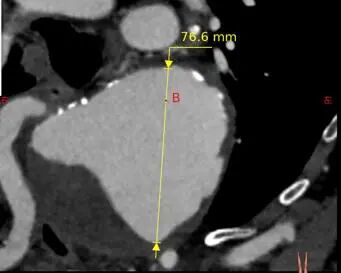

1、 根据CTA显示,患者的主动脉弓动脉瘤呈现囊状凸起并累及左锁骨下动脉(LSA)与迷走右锁骨下动脉,主动脉弓动脉瘤最大直径为76.6mm,有破裂风险,需要尽快手术治疗,决定采用腔内介入手术治疗。

治疗车怎么推【弓部重建直通车】梅州市人民医院心内科团队运用Castor®分支型支架联合预开窗技术治疗主动脉弓动脉瘤合并迷走右锁骨下动_https://www.jmylbn.com_新闻资讯_第4张

主动脉弓动脉瘤最大直径